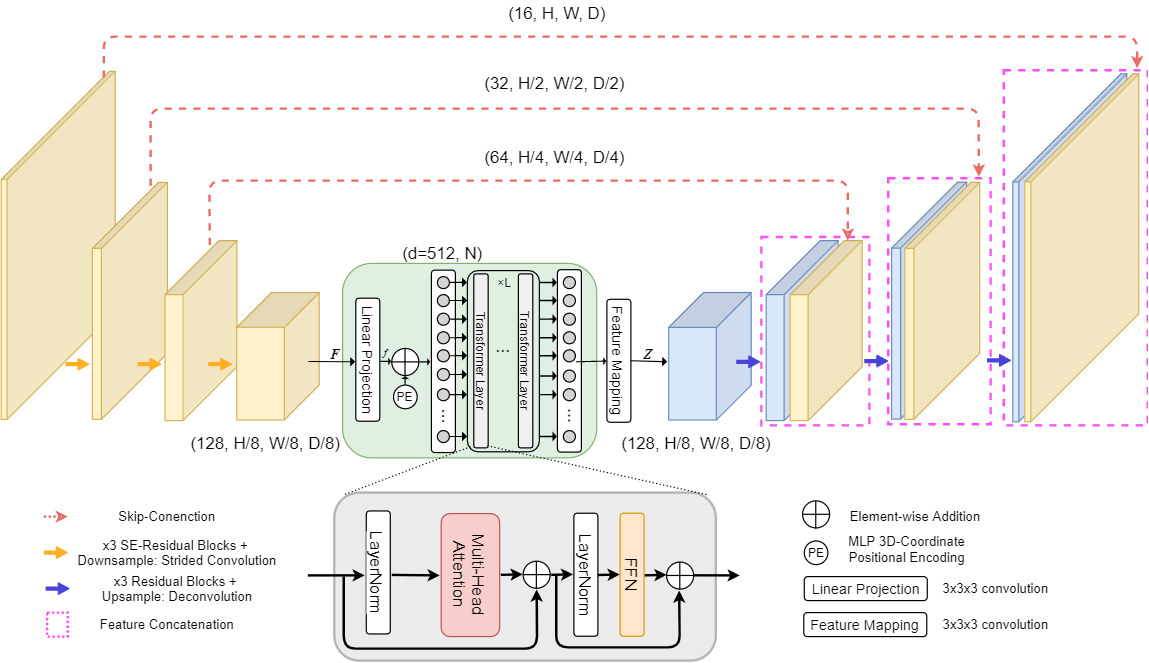

Our custom modifications (see Figure1 and Figure2 for comparison with original TransBTS):

-

•

We add Squeeze-and-Excitation blocks [5] to every layer of an encoder. SE blocks help perform dynamic channel-wise feature recalibration.

-

•

The depth of the model was increased compared to TransBTS by adding one layer in encoder and correspondingly in decoder.

-

•

We also replaced positional encoding from TransBTS with a learnable MLP block, for more details please refer to Section 2.4.